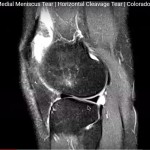

MRI in Medial Meniscal Tear

Courtesy: Robert LaPrade MD, Complex Knee Surgeon Steadman-Philippon Clinic, Vail, Colarado, USA http://drrobertlaprademd.com/ Address: 181…